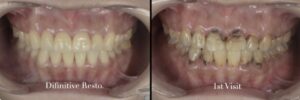

実際に症例を見てみましょう。

症例1

○患者情報

30代男性

これまでに他院様において複数回の前歯の歯科治療を行なってきたが、色や形が気になるとのことでした。ラミネートベニア治療に興味を持っており、相談のためにご来院されました。

歯には複数の施術を行なった痕があり、保険の材料(メタルやコンポジットレジン)を使用しているので色の不調和を認めます。

この方は中心位のずれという噛み合わせの乱れがある状況でしたので歯科矯正も同時に行なっています。

歯科矯正とラミネートベニアを用いて、咬合および審美面の改善を図りました。

⬆︎治療前⬆︎

⬆︎治療後⬆︎

咬合が安定すると、ラミネートベニアが破損せずに長持ちします。また、虫歯や歯周病にも罹患しにくい環境になるので歯も長持ちします。

大切な歯のために、患者様の将来を見据えた方針をご提案したいと考えています。ラミネートベニアを考えている方は、精密検査を行って包括的に口腔内の状態を把握することはとても大切かと思っています。